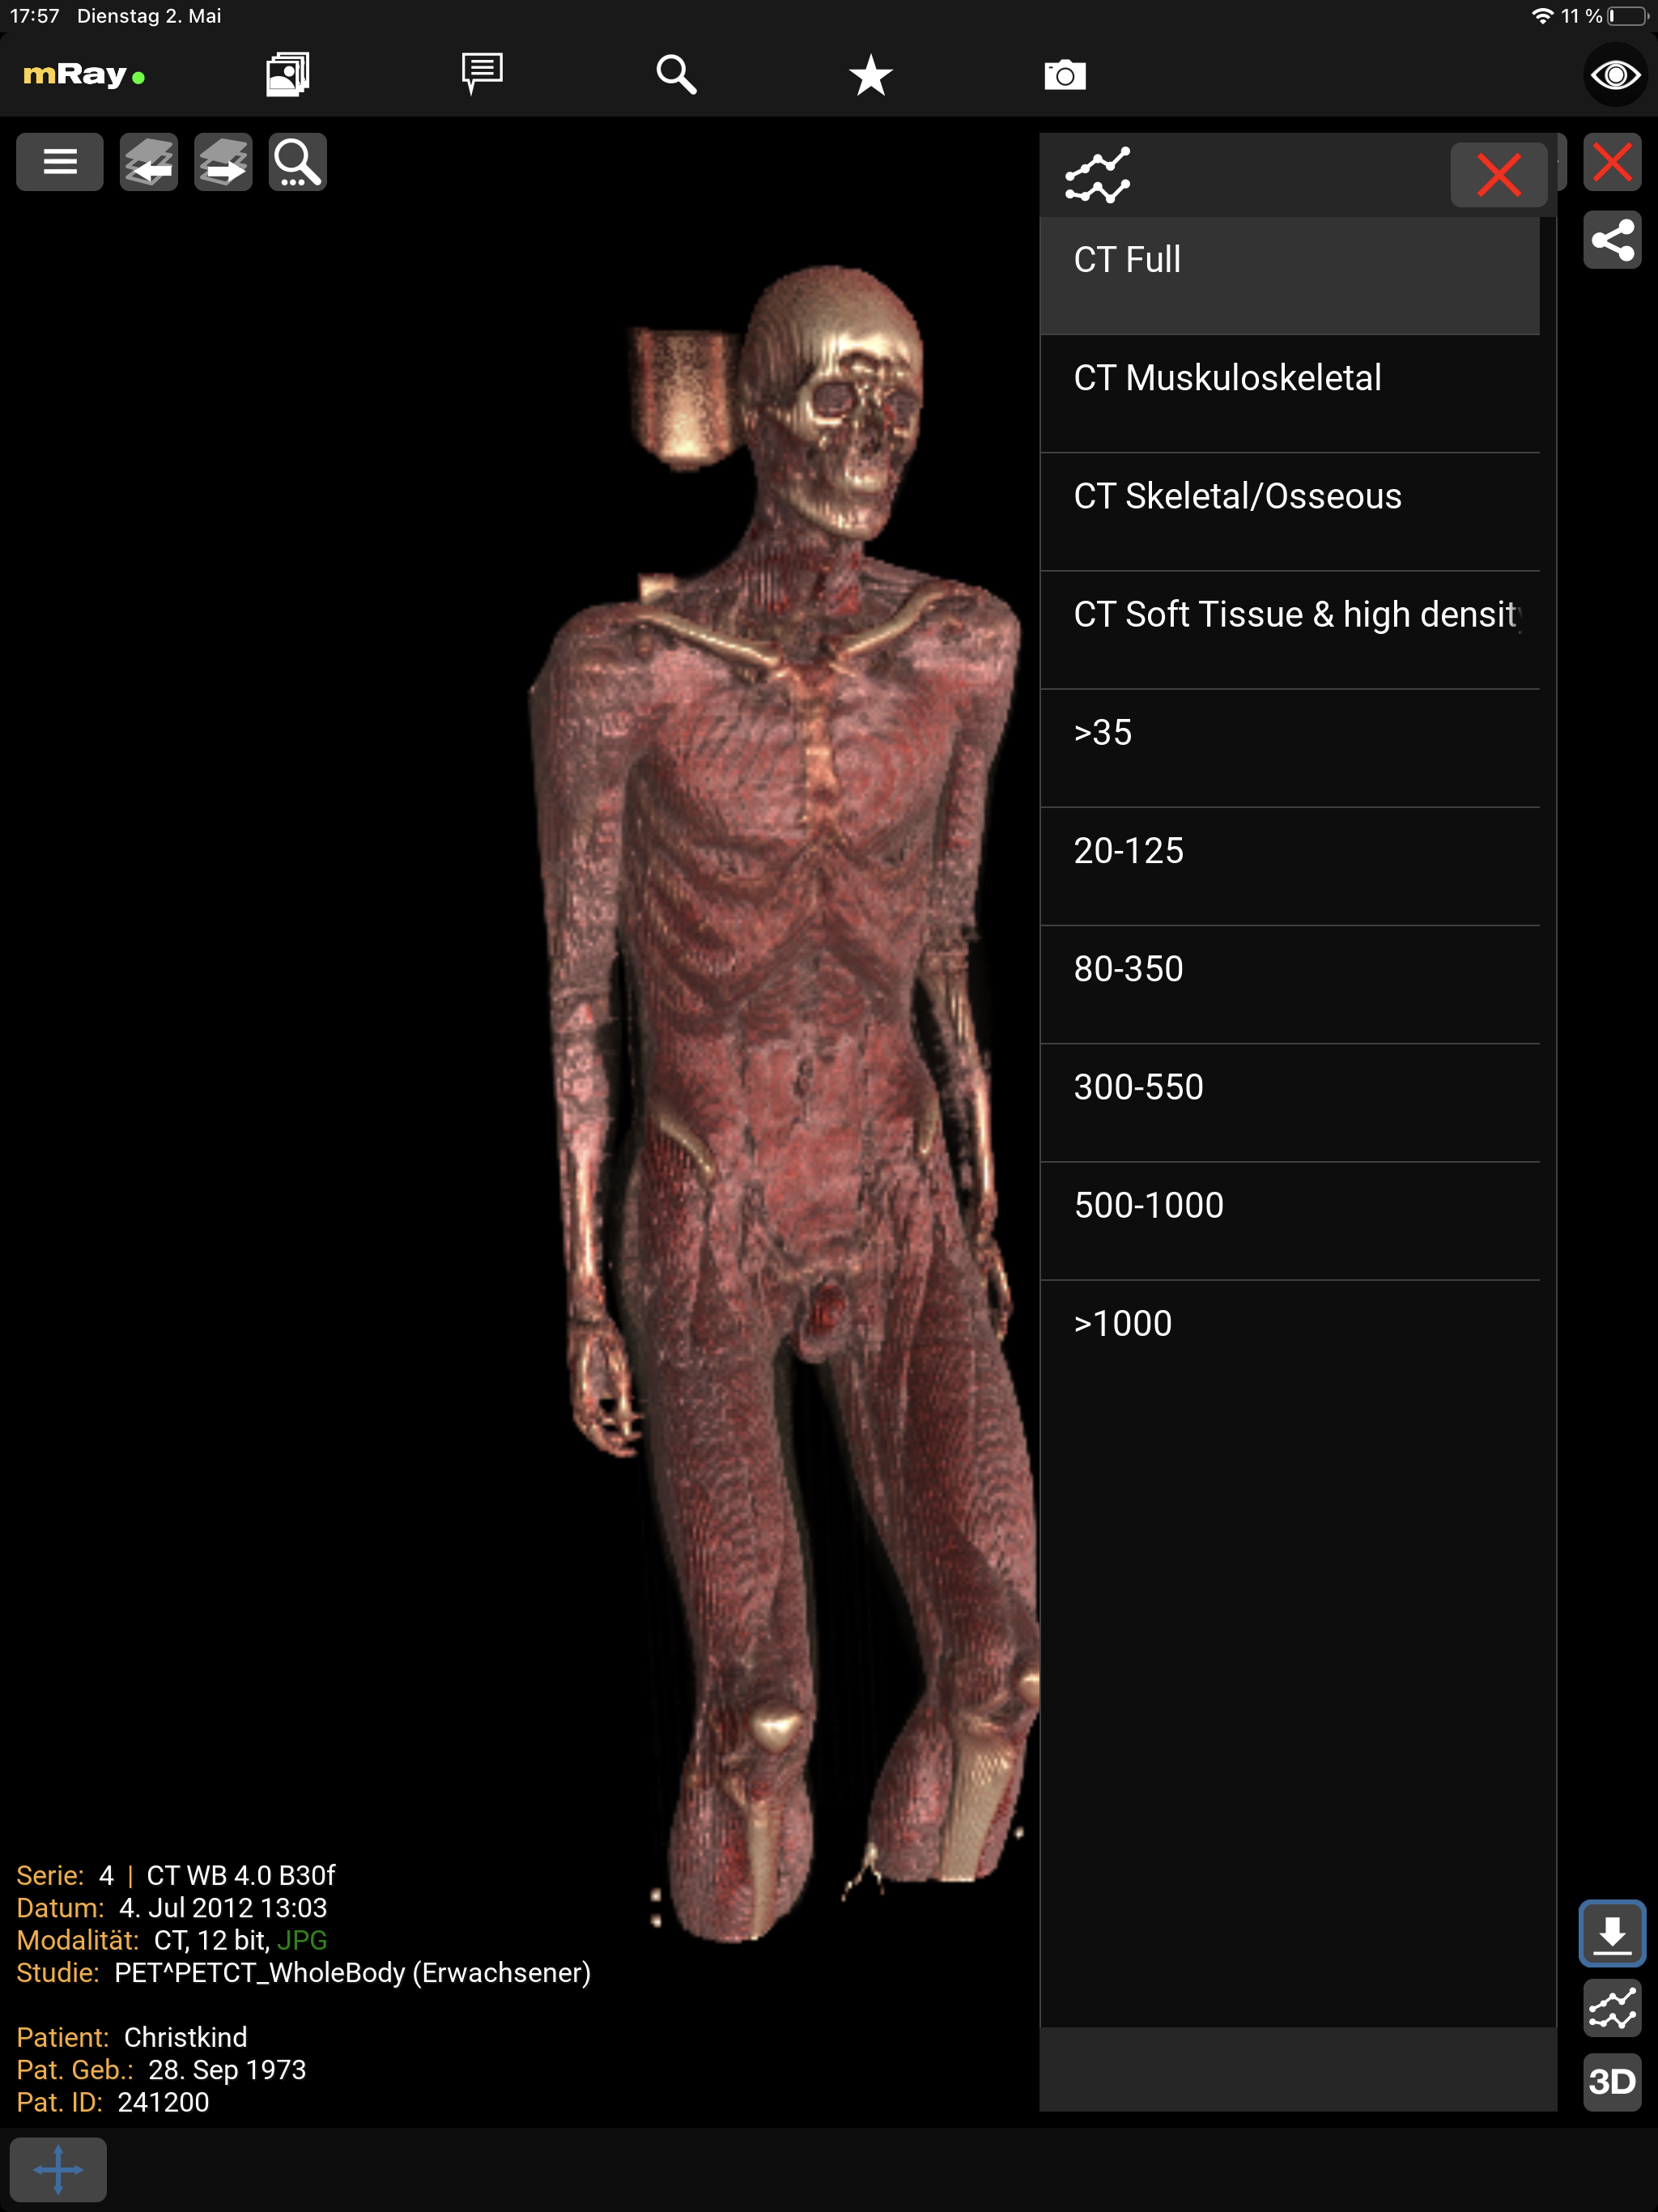

10.4.2. Volume Rendering

The Volume Rendering displays a CT or MRI dataset in 3D. To activate the functionality open the toolmenu, the volume rendering button appears for suitable datasets. The visualization can be adjusted by choosing pre-configured tissue or grayscale presets. With touch or left mouse button you can adjust the view direction. To zoom use the pinch gesture or right mouse button.

The screenshot shows the tissue or grayscale presets.

|

The visualization is only an approximation. Diagnostic decisions should be based on the conventional 2D visualization. |

|

Requires an OpenGL 3.0 capable device. Volume Rendering will otherwise be disabled. |